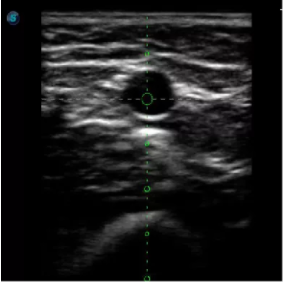

取卵臨床圖

傳統(tǒng)腔內(nèi)探頭采用直柄設(shè)計(jì),在搭配穿刺架使用時(shí),手術(shù)空間小,不易操作;生殖專用的曲柄探頭,探頭柄采用彎曲成角度設(shè)計(jì),可實(shí)現(xiàn)監(jiān)視、取卵兩不誤,搭載穿刺架時(shí),可以清晰顯示穿刺針的進(jìn)針過(guò)程、深度和位置,實(shí)時(shí)監(jiān)視取卵全過(guò)程,保障取卵操作精準(zhǔn)與安全。